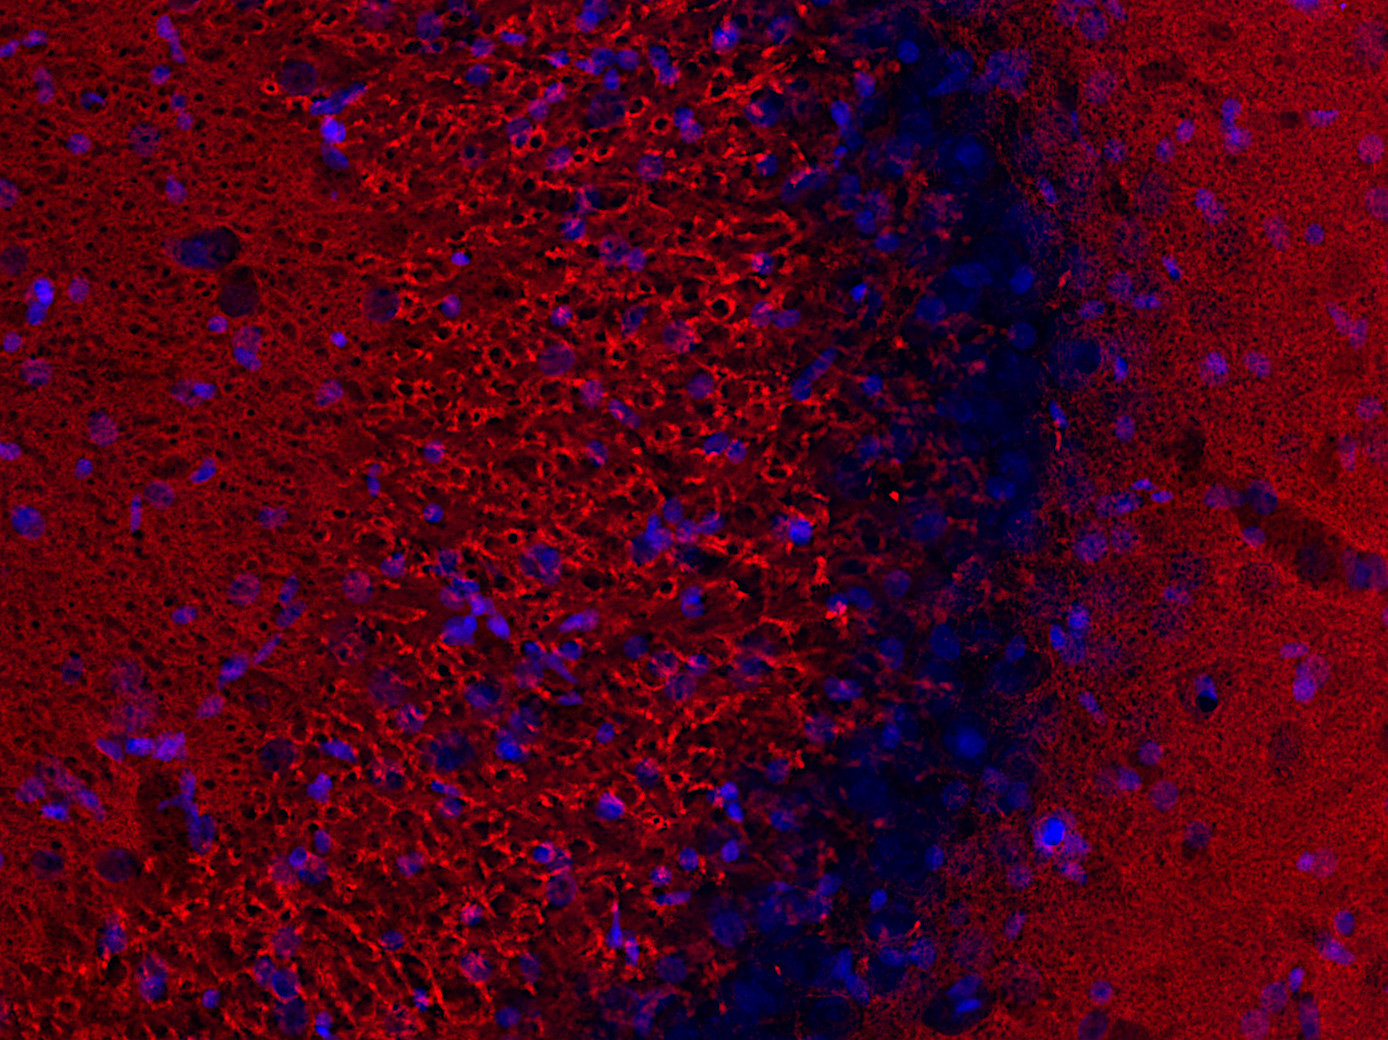

☆のん☆のん☆ 135302-ihc2.jpgの詳細情報

135302-ihc2.jpg。ALL STAR 100 GORE-TEX CHUNK Z SHIN-HI ブ。Notoginsenoside R1 - (3β,6α。☆ご覧頂き有難うございます☆☆商品詳細☆・ブランド :FURLA フルラ・商品名 :ハンドバッグ・トートバッグ・色 :イエロー系・柄(素材):レザー・サイズ :(約)タテ24cm ヨコ46cm マチ12cm・ハンドルの長さ:(約)52cm内側 :ファスナーポケット×1 :オープンポケット×2付属品 :なし ☆商品の状態☆使用感が少なく非常にきれいな状態です。AZONE INTERNATIONAL::からふるDreamin'::オールシリーズ詳細。・ベタつき:なし・剥がれ :なし・破れ :なし・金具類 :良好〇真贋鑑定済みの正規品実績のある大手業者間オークション『エコリング』からの商品です。ルイヴィトン バック。鑑定済みの正規品のみ販売しております。LeSportsac×神崎恵 PUFFY 2WAY BAGトフィーブラウン。〇こちらはクリーニング済みの商品となります■■返品・注意事項■■中古品につき、多少の汚れや傷はある物と理解頂き、ご購入ください。新品 未使用 エバゴス ¥74,800 トート ebagos シャンデリア。その他詳細はプロフィールをご確認下さい。【極美品】ヴァレクストラ イジィデ コインパース ショルダーストラップ。※完璧をお求めな方はご購入をお控え下さい。FENDI バイザウェイ ミディアム ネイビー ショルダーバッグ。※リペア品は、正規販売店で修理を断られる場合がありますのでご理解願います。LOEWE ブラック ショルダーバッグ ヘリテージ。【返金保証】・万が一正規品でない、明らかに写真・説明文と違うなど、こちらに不備があった場合は返品をお受けいたします。未使用★レアADMJはっ水 イタリアンレザー タンロック クロスボディーバッグ。-----◇-----◇-----◇-----◇-----◇-----◇-----◇-----◇-----◇【古物商取得済】東京都公安委員会 306702420364第号※即購入OKです。c*o様 ほぼ新品 Polo ID カーフスキン ミニ ショルダー バッグ。※ご不明な点がございましたらお気軽にコメント欄にてご質問下さい。【極美品☆袋カード付】デルヴォー ショート Dチェーン ショルダーストラップ。※ お値下げ可能な商品もございますので、お気軽にお声掛けください!-----◇-----◇-----◇-----◇-----◇-----◇-----◇-----◇-----◇#twinkle出品商品はこちらから管理番号:A-017汚れ・破れなど...なし